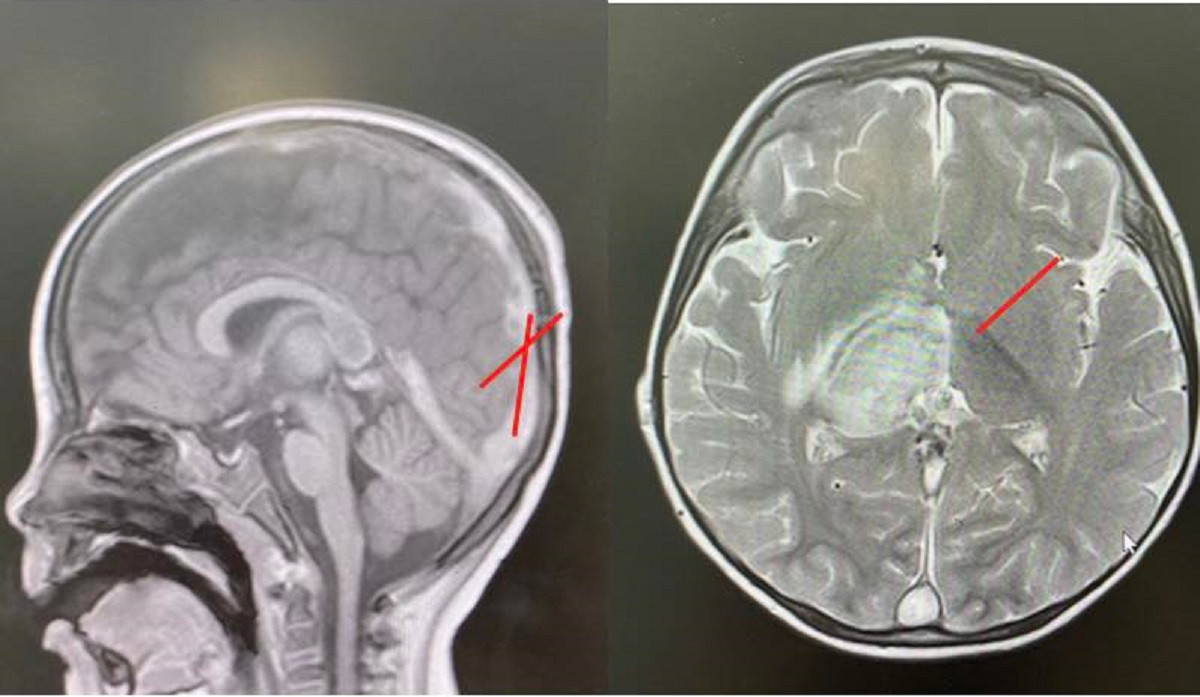

| Kết quả kiểm tra hình ảnh cho thấy huyết khối và tình trạng tổn thương não ở bệnh nhi (ảnh: BVCC) |

Các kết quả chẩn đoán hình ảnh cho thấy bé bị nhồi máu não vùng đồi thị, kèm phù não và huyết khối lan rộng trong hệ thống tĩnh mạch não – từ vỏ não, xoang tĩnh mạch nội sọ cho đến tĩnh mạch cảnh chung bên trái. MRI cũng ghi nhận xuất huyết trong não. Đây là dấu hiệu điển hình của huyết khối tĩnh mạch nội sọ (hay còn gọi là huyết khối xoang tĩnh mạch não).